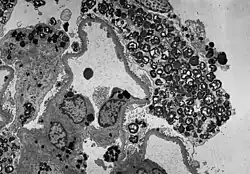

-

Histologisches Präparat einer mittels Biopsie entnommenen Hautprobe eines Patienten mit Morbus Fabry.

In der lichtmikroskopischen Aufnahme lassen sich die typischen Hautläsionen als kleine oberflächliche Angiome erkennen. -

Wie die meisten Symptome bei Morbus Fabry weist auch die Schädigung der Nieren einen progressiven Verlauf auf. Er endet mit dem terminalen Nierenversagen und bewirkt eine deutlich reduzierte Lebenserwartung.[70] Bei dem klassischen Krankheitsbild des Morbus Fabry führen die Gb3-Ansammlungen in den Endothelzellen des Glomerulums, in den Mesangiumzellen, in den Podozyten und in den Zellen des Interstitiums zur Schädigung der Niere.[71] Bei diesen Zellen handelt es sich um ausdifferenzierte Epithelzellen. Auch im Epithel der Henle-Schleife und des distalen Tubulus sowie im Endothel und den Zellen der glatten Muskulatur der Arteriolen der Niere finden sich Glycosphingolipid-Ansammlungen.[72][73] Im Transmissionselektronenmikroskop (TEM) sind die Gb3-Ablagerungen im Zytoplasma gut zu erkennen. Sie haben die Form von Myelinstrukturen und stoßen an den Zellkern. Mit zunehmender Gb3-Akkumulation wird das Mesangium aufgeweitet, worauf eine segmentale oder globale Glomerulosklerose mit Eindickung der Basalmembranen erfolgt.[74] Mikrovaskuläre Läsionen und Schädigungen der für die Filterleistung wichtigen Podozyten sowie der Epithelzellen des Tubulus werden dabei als mögliche Mechanismen diskutiert.[75]

- Gewebeproben aus der Niere von Patienten mit Morbus Fabry

Diese lichtmikroskopische Aufnahme zeigt die Akkumulation von Gb3 in den Endothelien des Glomerulums, in den Mesangiumzellen, den Zellen im Interstitium und in den Podozyten. -

Ebenfalls eine lichtmikroskopische Aufnahme. In den Podozyten ist die erhöhte Ansammlung an Gb3 durch eine violette Anfärbung sichtbar gemacht worden. -

Die TEM-Aufnahme zeigt die massive elektronendichte (= schwarze) Ansammlung an Glycosphingolipiden im Lysosom der Podozyten. -

Ebenfalls eine TEM-Aufnahme. Sie zeigt die Inklusionen von Glycosphingolipiden unterschiedlicher Form und Größe in den Zellen des distalen Tubulus. -

TEM-Aufnahme von den Endothelien und Zellen der glatten Muskulatur einer Nierenarteriole mit Inklusionen von Glycosphingolipiden